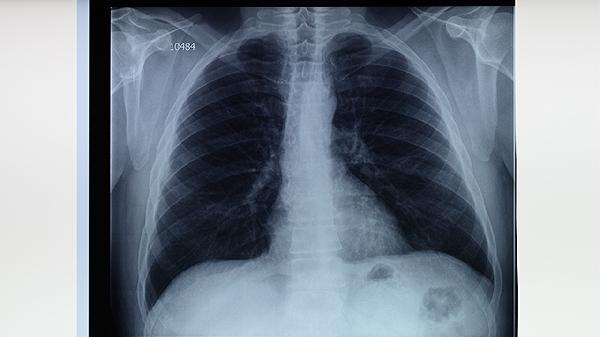

肺结核可通过中医辨证施治结合抗结核药物实现临床治愈,关键环节包括扶正祛邪、调理肺脾、清热解毒、活血化瘀、固本培元。

中医认为肺结核属"肺痨",正气不足时痨虫乘虚而入。治疗需用黄芪、党参等补益肺气,配伍百部、白及杀痨虫。临床常用百合固金汤加减,配合异烟肼等西药抑制结核杆菌,双管齐下提升疗效。

结核病灶局部炎性反应属热毒蕴结。黄芩、鱼腥草等清热解毒药能减轻肺部炎症,与利福平联用可降低耐药性风险。验方结核散含夏枯草、猫爪草等,对空洞型肺结核效果显著。

治疗期间宜食山药粥、银耳羹等润肺健脾膳食,避免辛辣燥热食物。太极拳八段锦等柔缓运动有助于恢复肺功能,但需避免剧烈运动耗气。保持居室通风干燥,每日艾灸足三里、肺俞穴各10分钟可巩固疗效。康复后每季度复查胸片,连续两年未复发视为临床治愈。需注意中医药起辅助作用,规范抗结核化疗仍是根治关键,任何治疗方案都应在专科医师指导下进行。